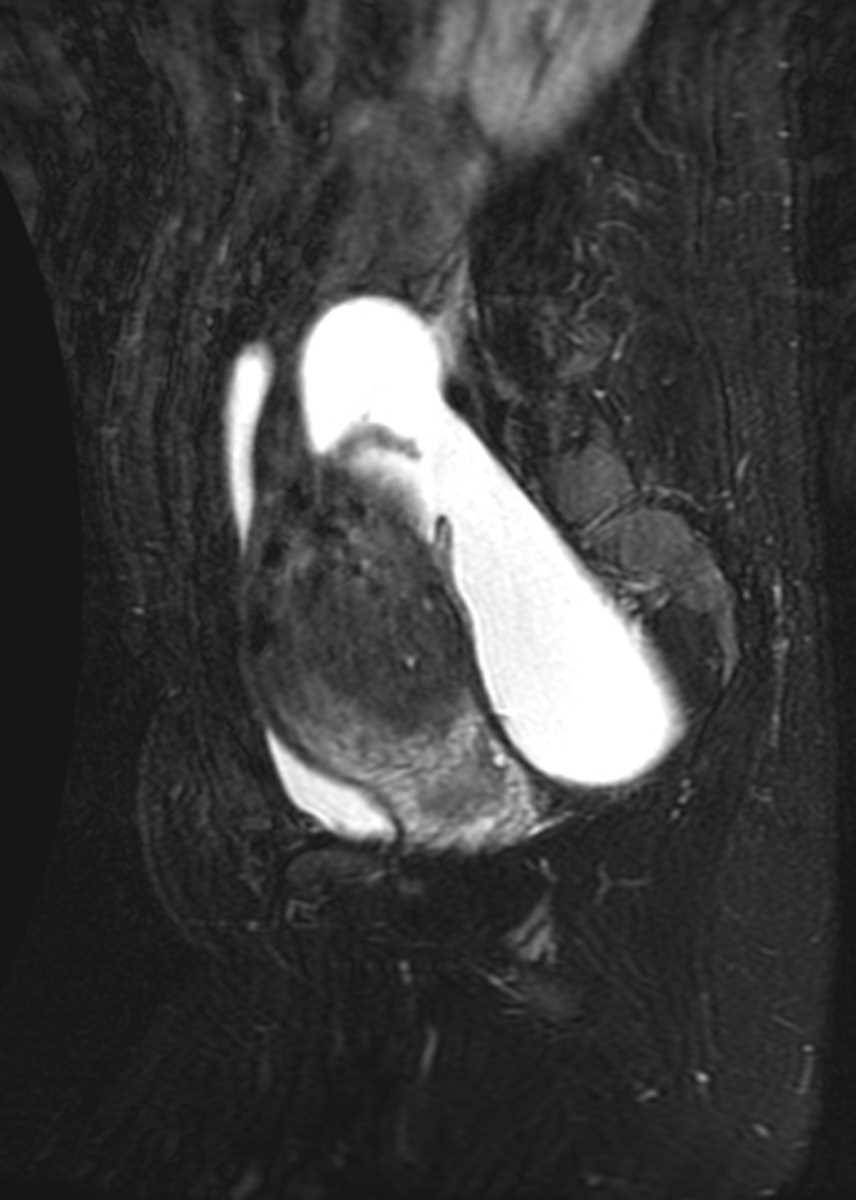

Uterine Adenomyosis

MRI images demonstrate massive thickening of the junctional zone of the uterus with multiple tiny T2 bright foci within this thickened junctional zone. The uterus is massivelt enlarged. This constellation of findings is consistent with uterine adenomyosis.